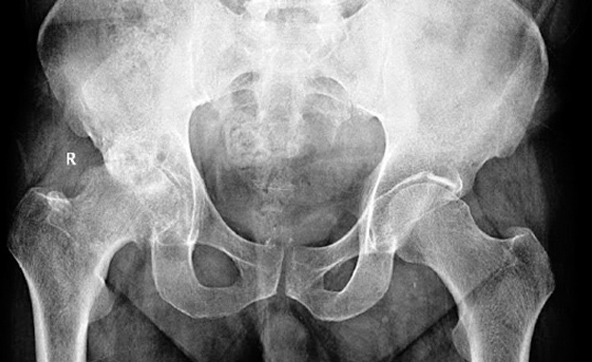

A veces las alteraciones son de origen congénito como la llamada Displasia congénita de la cadera y otras veces es secundaria como en el caso de una fractura o lesión de la cadera que, a su vez, puede dejar una secuela. Existen múltiples causas por la cual una cadera puede dar dolor o molestias y debe ser atendida por el especialista. Sin embargo, la más común es la degeneración o “envejecimiento” de la cadera llamada Coxartrosis o Artrosis de la Cadera La artrosis es un proceso degenerativo que se desarrolla en el cartílago y disminuye su grosor por pérdida de la capacidad de retener agua. El espacio articular va disminuyendo de altura y se ve en la radiografía simple como un pinzamiento en la articulación. A medida que la persona envejece, la frecuencia de la artrosis de cadera va aumentando. Pero no es sólo la edad el factor que hace aparecer la artrosis, también lo hace el uso exagerado de la cadera (sobrepeso, actividades físicas exageradas, etc.) y algunas patologías tanto locales como generales.

La cadera joven presenta un cartílago liso, transparente, grueso y de color acerado. Con el uso, este cartílago va disminuyendo de espesor, se hace opaco, de menor elasticidad, menos brillante y amarillento. En las superficies de carga se hace menos liso y poco a poco se va erosionando hasta quedar sin cartílago (envejecimiento articular) Otras veces se debe a alteraciones locales de la cadera o secundarias a enfermedades que afectan indirectamente a las caderas.